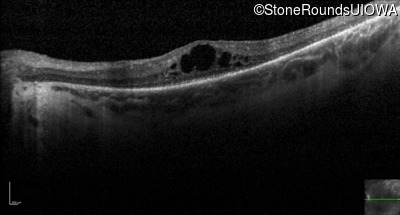

Optical Coherence Tomography - Left - 20/70 +1

Exemplar / OCT Stack